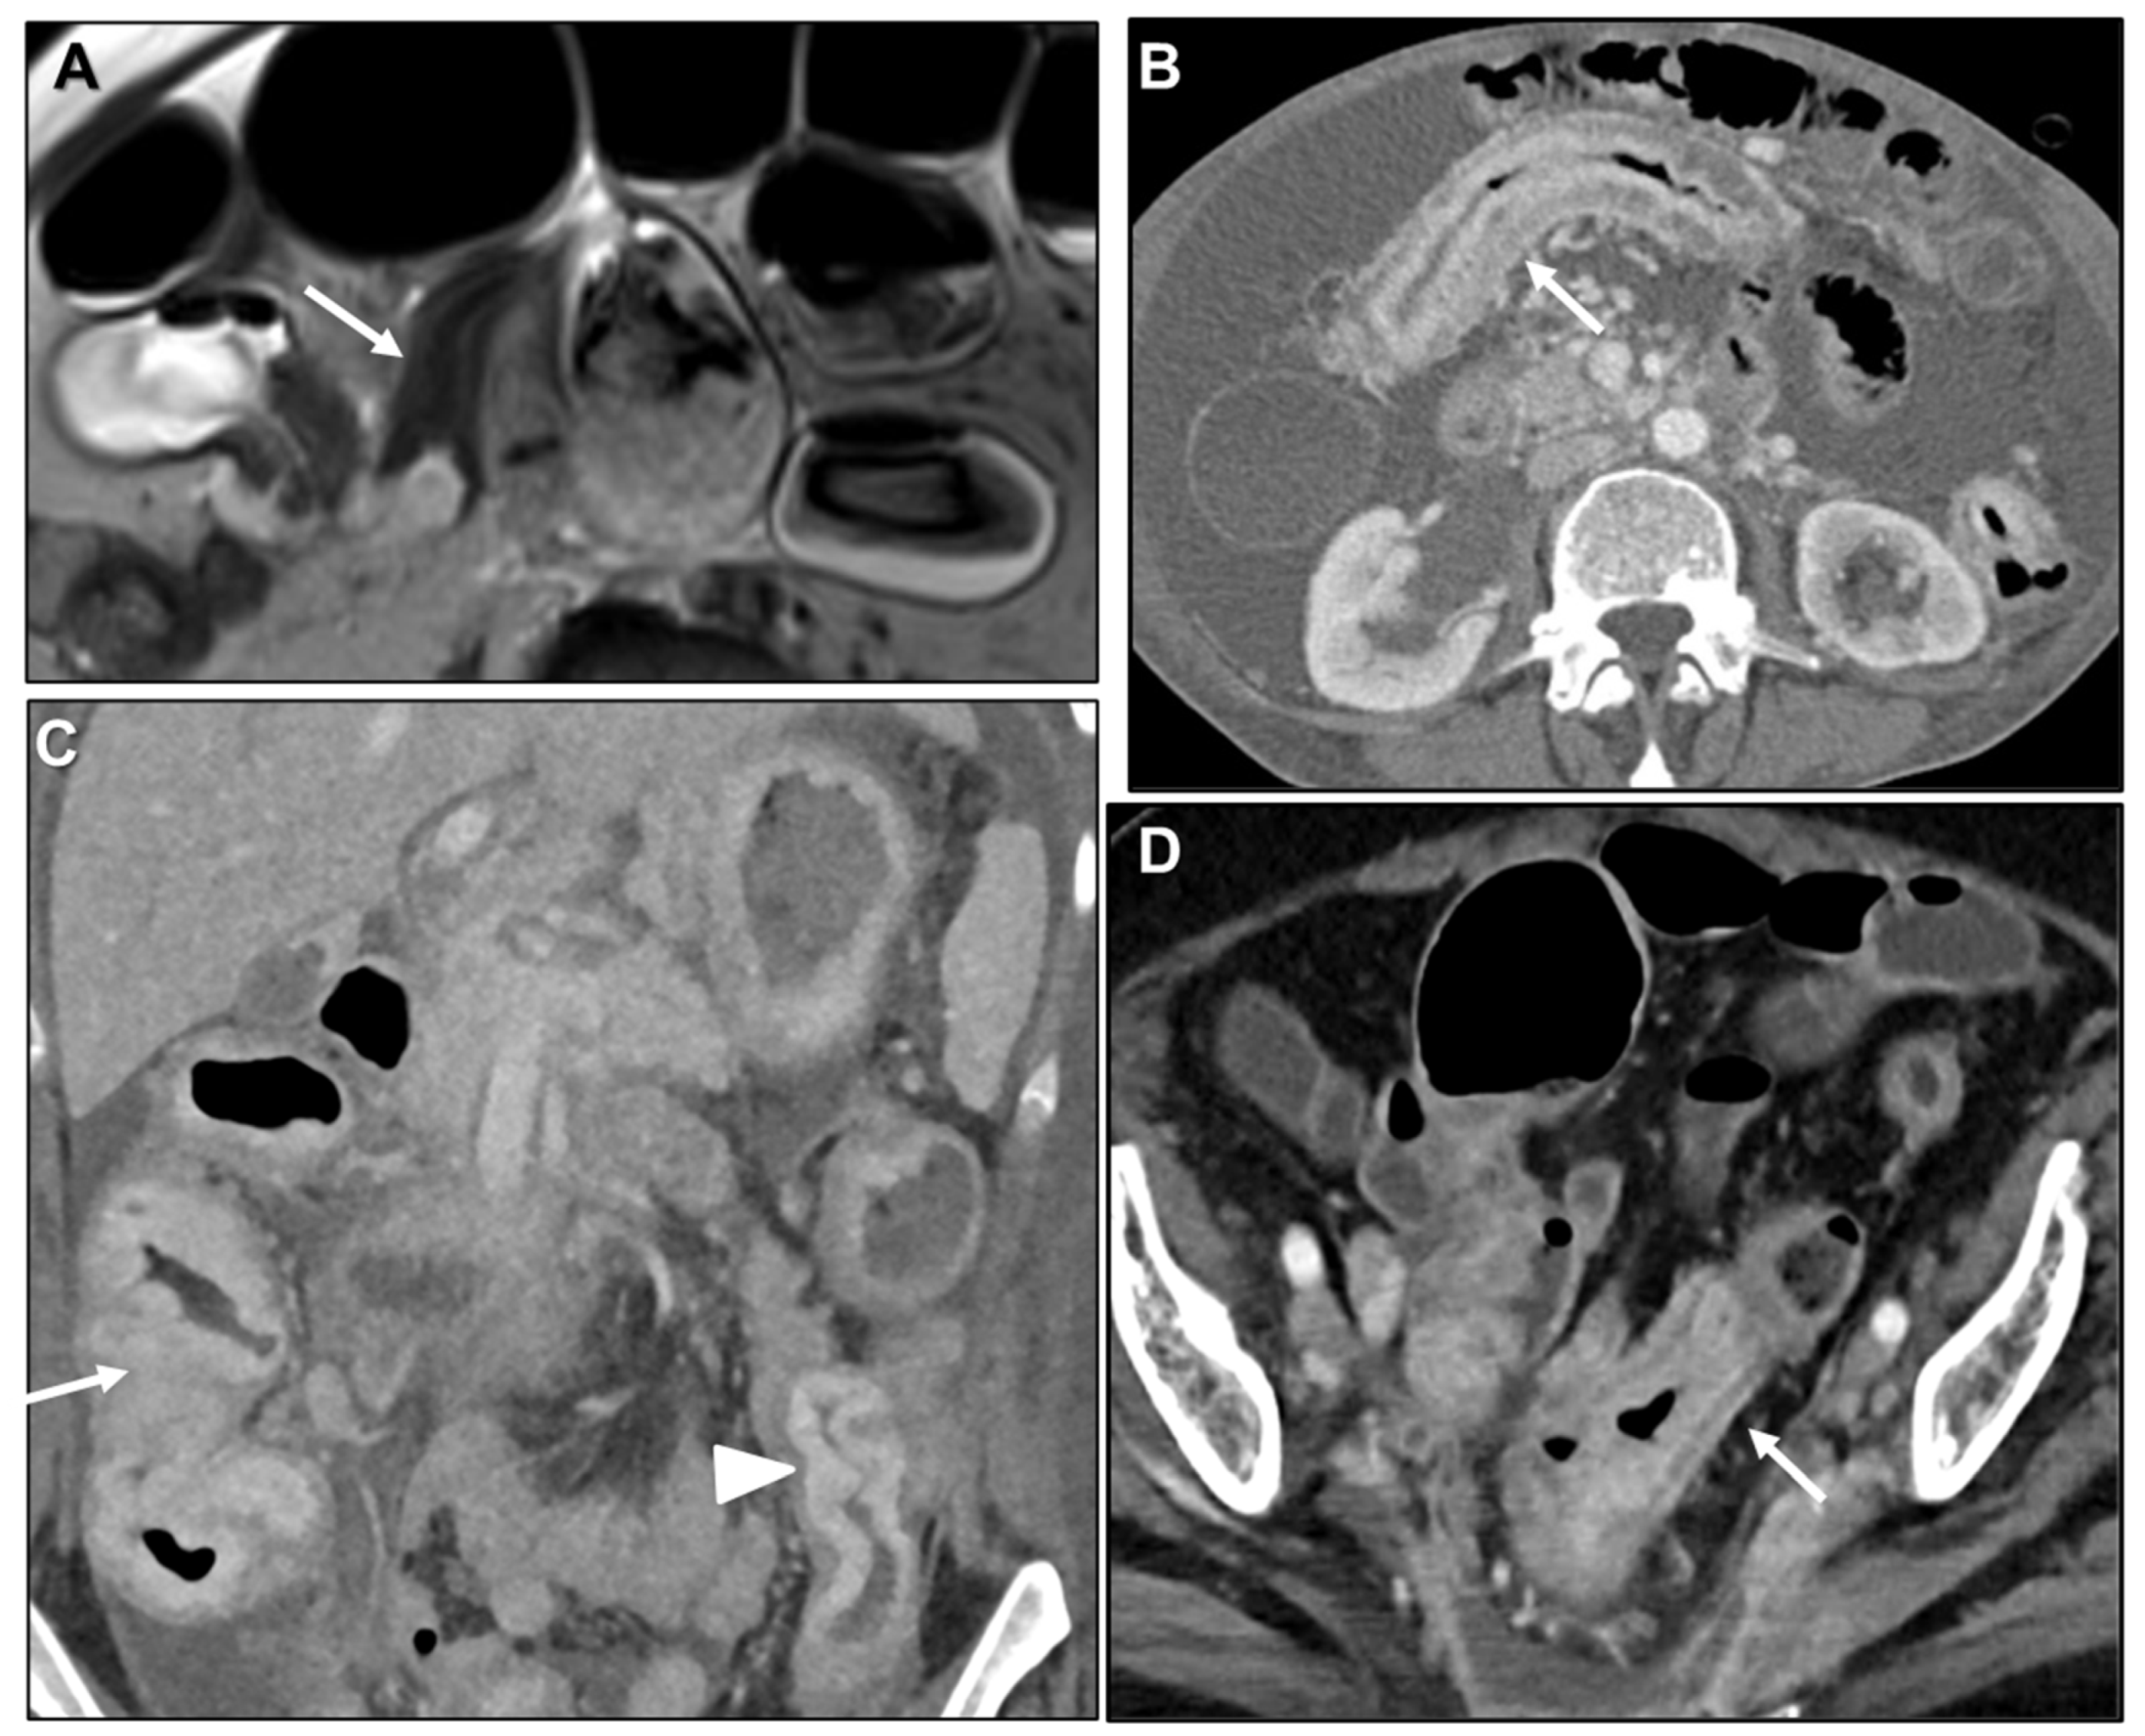

Malignant Target Sign

Homogeneous Delayed Enhancement

Concentric Ring Pattern

Length

2.2.2. Associated Imaging Features